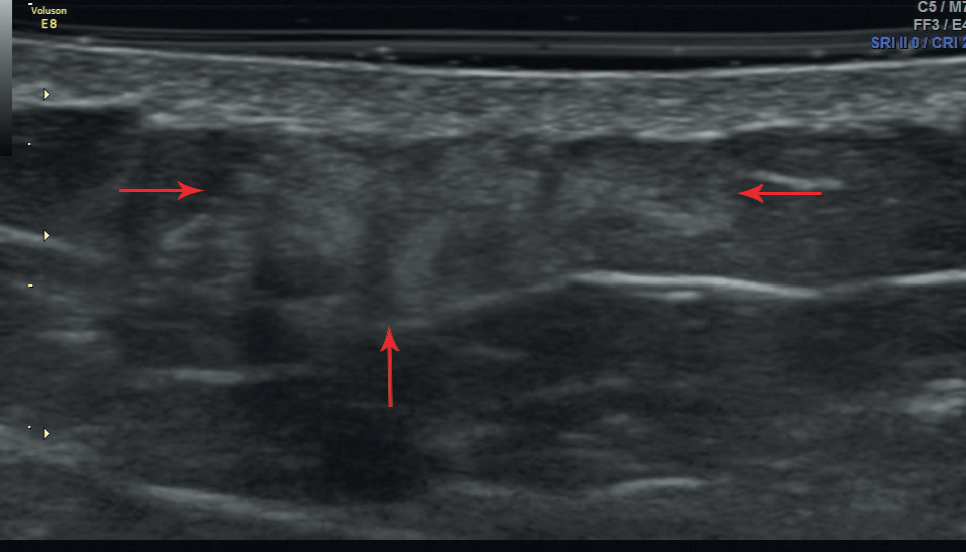

5. Fig. 1. Hyperechoic part of lipohypertrophy in the subcutaneous tissue of the anterior abdominal wall in the area of insulin injections in a patient with diabetes mellitus. S-scan in B-mode. | |